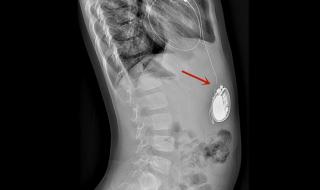

全磁浮心脏即离心泵人工心脏,被称为第三代人工心脏,是目前最先进,对人体影响最小也是最耐用的人工心脏,美国FDA前两年刚上市了第一款,我国高端医疗器械几乎无国产产品。